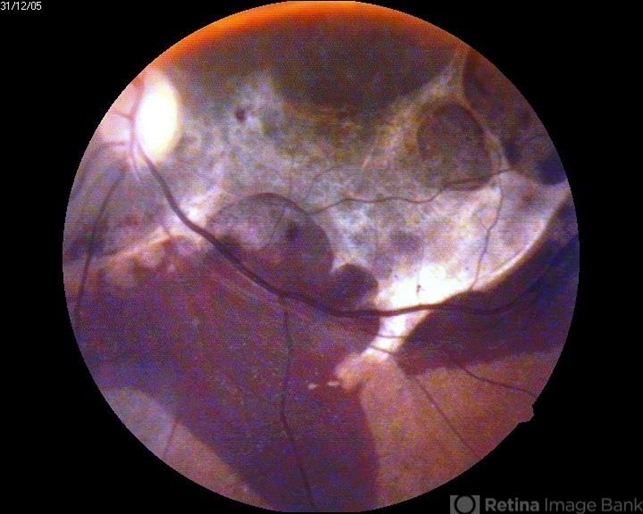

- subretinal fibrin deposition

- A 30-year-old male presented to us with history of blunt trauma before few months, he was found to have subretinal hemorrhage and fibrosis.